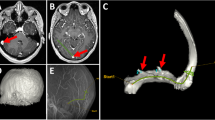

In addition, filling of deep distal cerebral veins appeared uneven, possibly due to brain edema caused by flushing of the ICAs with saline under too high pressure. Therefore, the volume of saline was reduced, and saline was injected more slowly. Cadaver heads injected after application of a neck tourniquet showed improved cerebral venous filling. Though, elevated pressure during injection resulted in extravasations of the radiopaque injectate in two heads. Extravasations were encountered in relation to intra- and extracranial dural surfaces (Fig. 2a, d).

a Posterior view of the cerebellum and confluence region during dissection in specimen. Before durotomy, smaller strings of extradural free extravasations of injectate around the confluence, superior sagittal sinus and bilateral transverse sinuses via Paccionean granulations (white arrows). b Posterior view of the cerebellar hemispheres after durotomy showing a filling defect (red arrow) in the midline: in the inferior vermian vein on the right side. c Radiograph, lateral view shows filling defects in the Vein of Galen as well as the straight sinus (red arrows). d Radiograph, AP view shows extravasation (leakage) from the superior sagittal sinus or cortical veins (red arrows) (color figure online)

For each cadaver head, radiographic images of both the superficial and the deep venous systems of the brain showed filling of veins down to 150 \(\mathrm{\mu m}\) in diameter (Fig. 3a, b). With the optimized injection technique, the heads had a more homogenous cast allowing better discrimination between vascular structures and brain tissue during dissection. The venous anatomy in the quadrigeminal cistern was chosen as the area of reference among the seven scanned and dissected heads. We managed to identify both larger vessels and sinuses and smaller vessels and tributaries on parallel dissection images and 3D reconstructions as shown in Fig. 3b, c. During dissection, the brain preparation allowed realistic retraction and manipulation during microsurgical instrumentation and was found to be a suitable model to practice neurosurgical approaches. Dissections carried out more than 6 months after cadaver preparation and injection had these qualities preserved.

a Lateral projection of a cadaveric head injected with a 25% latex-barium mixture into the internal jugular veins. High-resolution visualization of the Galenic system and posterior fossa veins. b Volume rendering technique (VRT) after cone-beam CT showing the same anatomy in 3D with significantly more details. c Surgical dissection of the same specimen showing the same anatomy in posterior view. Arterial injection was done with red latex and no barium

Extravasations of the radiopaque injectate impaired 3D visualization in certain locations (Fig. 2d). This can possibly be avoided by improving positioning of the catheter before injection to confirm that the catheter is not blocked by a blood clot risking sudden excessive pressure on the syringes.

Intraluminal filling defects may be caused by compression of thin-walled vessels from cerebral edema, residual fixative, saline or blood clots (Fig. 2b, c).